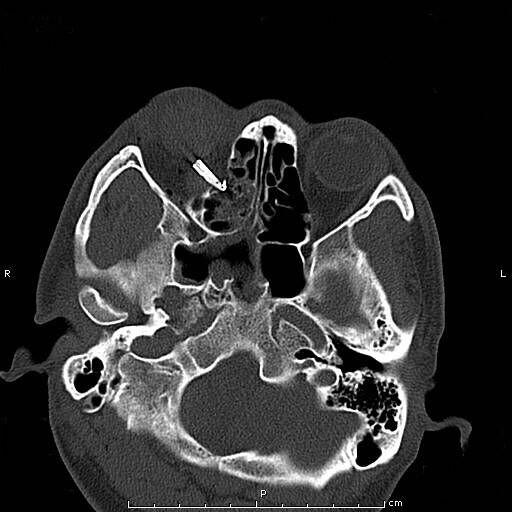

患者青年男性,因“右眼被鋼筆戳傷2小時余”入院,眼科查體:視力:右無光感,左0.4。眼壓:右不能檢查,左正常。右眼上瞼紅腫,鋼筆自顳上方眼瞼刺入,末端位置不詳,睜眼困難;結(jié)膜充血、水腫,角膜尚清,前房積血,余眼內(nèi)結(jié)構(gòu)窺不入。左眼未見明顯異常。入院后完善眼眶CT檢查,印象:右眼眶異物并右眼球破裂傷、眶內(nèi)壁骨折,異物嵌頓于眶壁。鋼筆內(nèi)含墨水,傷情重且復(fù)雜。

經(jīng)科室討論、充分評估患者病情,與患者進(jìn)行病情溝通后,擬于全麻下實施右眼眶壁異物取出+眼球破裂傷清創(chuàng)縫合探查+眼瞼皮膚裂傷清創(chuàng)縫合+萬古霉素玻璃體腔注藥術(shù)。由于鋼筆筆尖與筆筒游離且筆尖彎曲倒鉤于眶壁,使異物取出難度大大增加,經(jīng)專家團(tuán)隊討論,決定在鼻內(nèi)窺鏡協(xié)助下聯(lián)合眶內(nèi)入路分離、截斷內(nèi)直肌、下直肌成功將眶內(nèi)壁異物自鼻腔完整取出,手術(shù)取得圓滿成功。